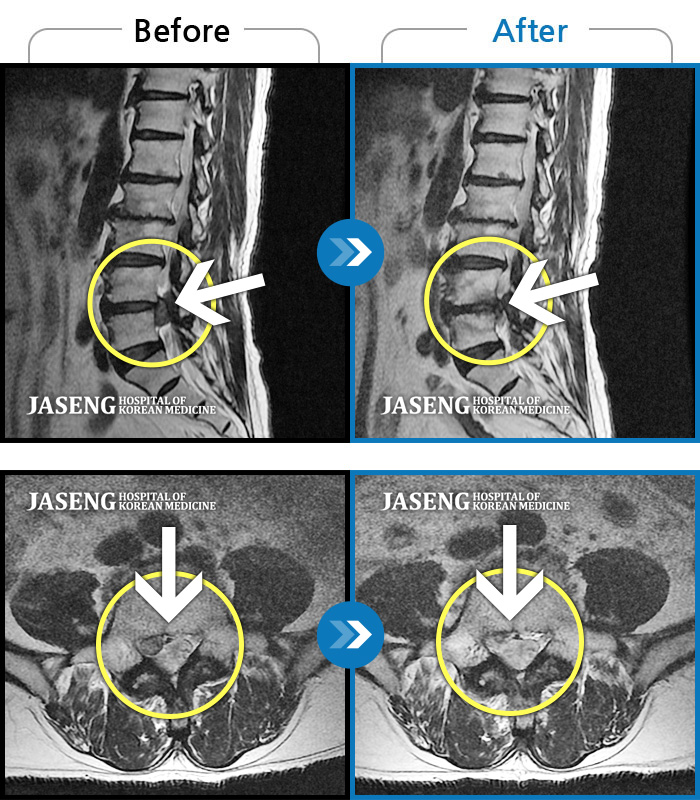

허리디스크

일산 · 김진수 원장

처음 내원 시 허리, 엉덩이가 많이 아프고, 좌측 다리로 근력 및 감각 저하도 있었으며, 야간통을 잠도 못자고 통증 심하여 식사도 무릎꿇고 하는 등 정상적인 활동이 힘든 상태셨습니다.

촬영시기

2022.11.16 ~ 2023.05.24

2023.06.01